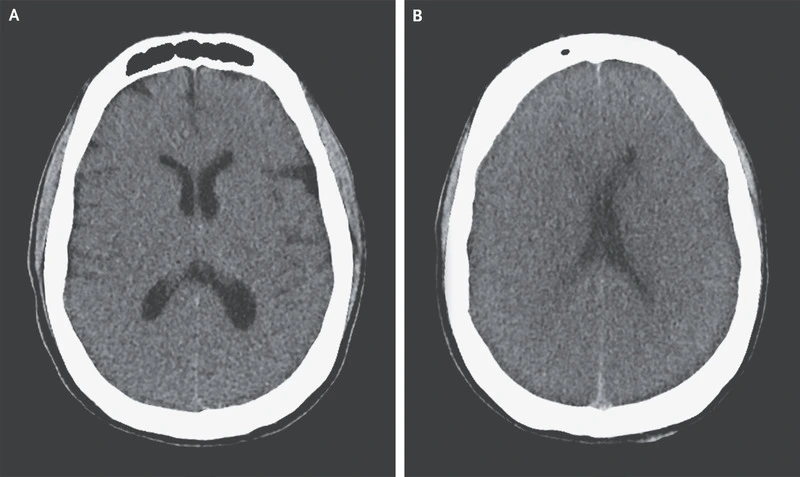

환자의 뇌 CT 결과는 암울했다. 뇌사 상태였고, 지금 당장 심정지가 와도 이상하지 않은 상태였다. 수술은 의미가 없었다. 살아날 가능성은 전혀 없으니까.

응급실에 내려온 내가 할 수 있는 일은 제한적이었다. 뇌 CT 영상에 나온 환자의 뇌는 새카맣게 괴사되어 있었다. 뇌사 상태로, 어떠한 치료도 가망이 없다는 뜻이다. 다른 환자들처럼 '수술해도 죽는건 마찬가지지만 최대한 버틸 수 있게 도와드립시다'라는 개념으로 수술하는 것도 가망이 전혀 없는 상태였다.

brain death.jpeg 뇌사 환자의 뇌CT 영상. 뇌사환자의 의식이 돌아올 가능성은 없다. DM Greer, Determination of Brain Death, NEJM, 2021.